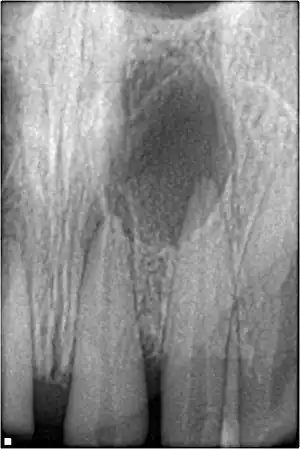

![]() | |

| A broken upper front tooth. The layers of tissue that make up the tooth are clearly visible, with the pink pulp standing out against the paler dentine and tooth enamel. | |